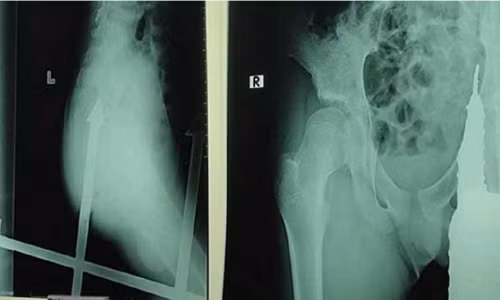

| Cọc sắt đâm vào mông bé trai rất nguy hiểm. |

Tại bệnh viện, bác sĩ kiểm tra và phát hiện, vị trí đâm chỉ cách hậu môn của bé vài milimet, rất nguy hiểm. Sau khi kiểm tra, bác sĩ lập tức đưa bé trai vào phòng phẫu thuật. May mắn thay, ca phẫu thuật thành công, cọc sắt nhọn được lấy ra khỏi cơ thể bé. Hiện tại tính mạng của cậu không còn nguy hiểm, tuy nhiên vẫn phải theo dõi để tránh nhiễm trùng.